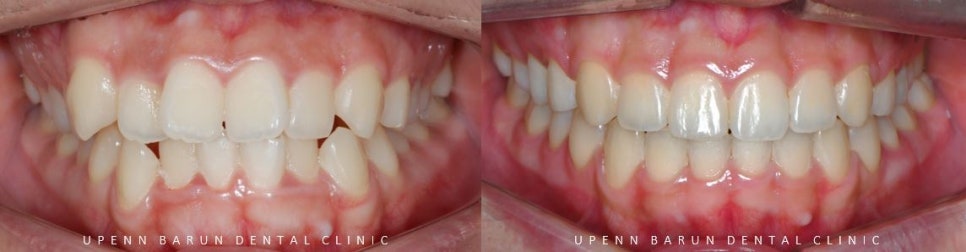

교정기간 21/6 ~ 24/2

위 사진은 윗니 아랫니가 접촉되는 면을

spot 으로 나타내주는 사진 입니다.

교정 전에는

중요한 역할을 하는 송곳니가

맞물리는 치아 없이 제 기능을 하지 못하고 있었지만

교정 후

삐뚤빼뚤했던 치아들이 제 위치를 찾으며

심미적으로 개선이 되었을 뿐만아니라

송곳니 등 치아의 역할이 기능적으로 개선이 되었습니다.

위, 아래 앞니가 정확히 맞물리지 않았던 이전과는 달리

악궁확장기능이 있는 데이몬 교정을 통해 '발치를 하지 않고'

치아들이 제 자리를 찾으며

가지런히 펴졌는데요 ^^